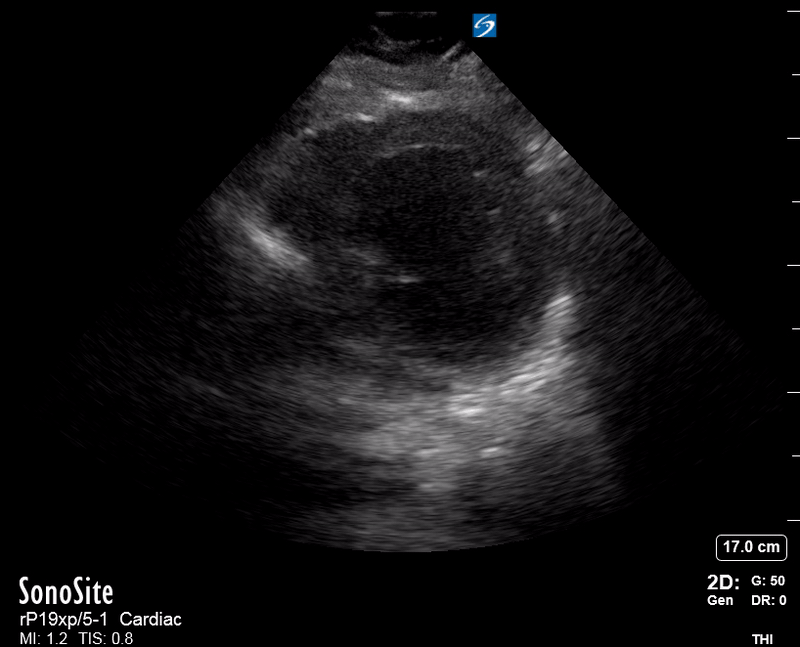

The PLAX view is versatile and allows the recognition of multiple landmarks, making it good for visual estimation of LV contractility. It is essential to optimize the view ensuring a true sagittal long axis, as being oblique to the LV chamber may underestimate its size and overestimate its emptying. The PSAX view at the level of the papillary muscles reveals the entire muscular circumference and concentric squeeze of the LV. It is useful to estimate both global function and focal wall motion abnormalities. The A4C view, although technically challenging, provides good insight into the global myocardial function and chamber size.

LV CONTRACTILITY

Qualitative assessment of the LV and visual estimation of Ejection Fraction is based on three parameters:

Endocardial excursion.

Myocardial thickening.

Movement of the anterior leaflet of the mitral valve.

A qualitative assessment is typically categorised as:

Normal (LVEF 50-65%)

Moderately Depressed (LVEF 30-50%)

Severely Depressed (LVEF < 30%)

Hyperdynamic (LVEF > 65%)

SIGNIFICANTLY IMPAIRED / DILATED LV

A severely depressed LV contractility, particularly when paired with a plethoric IVC or lung B-lines, indicates systolic heart failure. Chronically raised afterload can lead to severe dilation of the LV.

In contrast, hyperdynamic states are associated with decreased afterload and are classically found in patients with sepsis or severe hypovolaemia. A hyperdynamic heart should be accompanied by a small, collapsing IVC. Moreover, is essential to remember that tachycardic is not the same as hyperdynamic, as the latter is a measure of contractile activity and emptying. A tachycardic heart is not necessarily hyperdynamic.